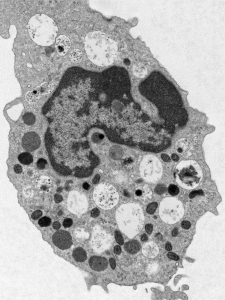

Allergic asthma is a complex condition characterized by pulmonary inflammation, increased mucus production, and epithelial remodeling, pulmonary inflammation, and increased mucus production—factors that contribute to airway constriction and breathing difficulties. Interestingly, individuals with asthma experienced reduced morbidity and mortality compared to the general population during the 2009 H1N1 influenza (swine flu) pandemic. Using murine models of allergic asthma which exhibit pulmonary eosinophilia, our lab demonstrated that eosinophils engage in crosstalk with CD8⁺ T cells leading to, decreasing reduced viral load and influenza pathophysiology. The Samarasinghe Lab investigates the underlying mechanisms of this response, focusing on the transcriptional regulation, immune cell interactions, and differentiation of eosinophil populations during respiratory viral infections.

Eosinophils are traditionally recognized for their protective role against helminth infections, but they also possess antibacterial capabilities. Using a murine model of allergic asthma marked by eosinophilia, the Samarasinghe Lab discovered that mice with allergic inflammation exhibited reduced mortality, lower Streptococcus pneumoniae bacterial loads, and decreased lung damage and inflammation following co-infection with influenza A virus and S. pneumoniae. The lab is working to uncover the mechanisms by which eosinophils detect and eliminate opportunistic bacterial pathogens in the respiratory tract.